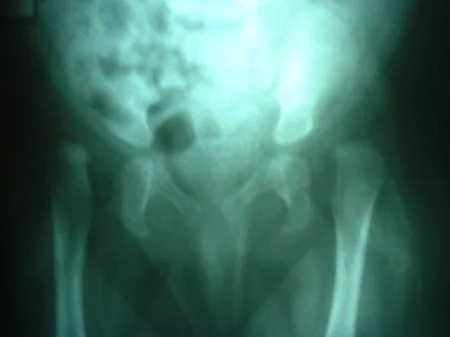

Cadera

La Displasia del Desarrollo de la Cadera ó Displasia Evolutiva de la Cadera, es un problema dinámico que abarca un amplio espectro de condiciones patológicas, clínicas y radiológicas, que incluyen desde  la cadera luxada, subluxa y la inestable, pasando por la displasia o alteración del desarrollo acetabular o de la cabeza del fémur. Ver más.